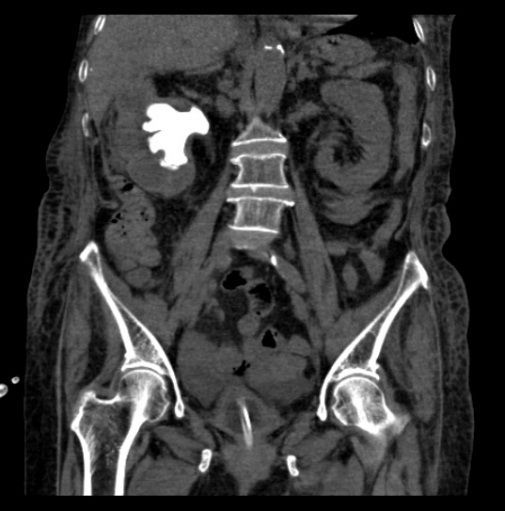

住院后完善检查后发现,患者3年前因右肾结石并积脓感染在外院行右肾穿刺造瘘后1月拔出造瘘管,之后从造瘘管持续流出脓液至今,单单是更换纱布的花费已有2万余元。

因患者存在严重的泌尿系感染,长期感染致使患者出现严重营养不良及毒素缓慢吸收的中毒表现,遂全科讨论后首先尝试行右侧输尿管支架植入术以求内引流控制感染,但效果不佳;果断再次行右侧肾穿刺造瘘引流局部感染物质控制感染!

感染初步得到控制后,

明确患者右侧肾铸形结石

并右侧无功能肾,

黄色肉芽肿性肾盂肾炎( xanthogranulomatous pyelonephritis,XGP) 是一种少见的由细菌感染引起的肾实质及肾周组织慢性非特异性炎性病变,约占所有肾感染的0. 6% ~ 1. 4%,由于发病率不高,缺乏特异的影像学表现,常常被误诊为恶性病变。

当患者出现发热、腰疼、血尿、脓尿、尿路刺激症状以及合并慢性泌尿系梗阻症状时,结合以下声像图改变,包括肾形态饱满、肾盂扩张积水,扩张集合系统内具有低回声,尤其发现病人有泌尿系梗阻原因及肾结石时,可以考虑到XGP 的可能性。CT 和超声造影可能有助于进一步明确疾病的诊断,最终确诊仍需依靠超声引导下穿刺或手术的病理报告。